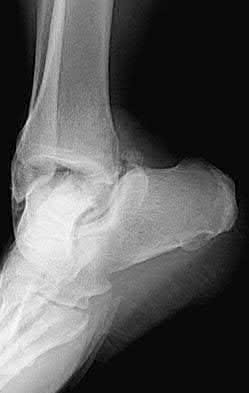

2. # A 35-year-old woman is involved in a head-on collision while driving. Initial radiographs are shown in Figures 8a and 8b. Injury to what vessel increases the risk for osteonecrosis of the injured bone?

5. Artery of the tarsal sinus Corrent answer: 4

The patient has a Hawkins type III talar neck fracture-dislocation with a risk of osteonecrosis ranging from 69% to 100%. Anatomic studies have shown that the artery of the tarsal canal supplies the lateral two thirds of the talar body.

The other vessels listed provide no significant contribution to the talus.